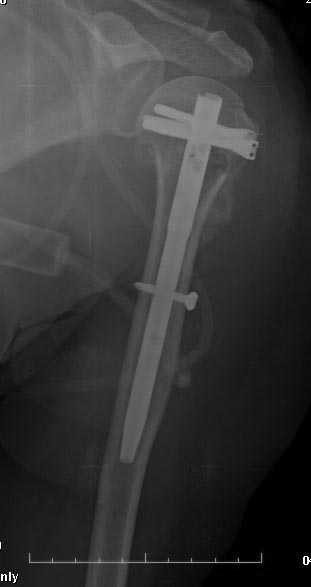

[Ortho] Перелом проксимального отдела плеча

по-другому. НаучИтесь - понравится. Вот примерчик, операция закрыто

через 2 мес. после травмы.